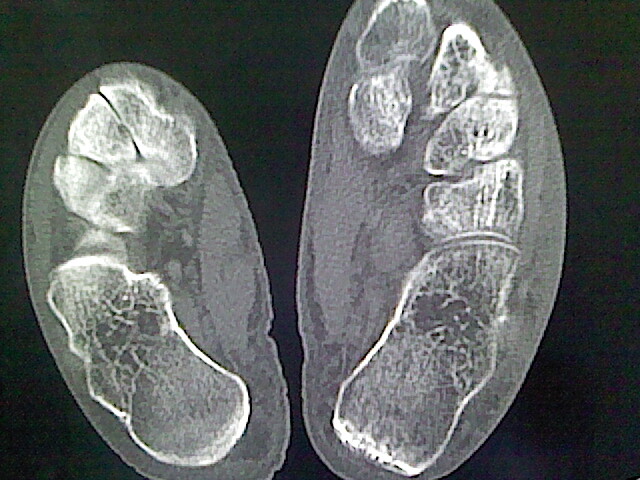

色素沉着绒毛膜结节性滑膜炎可能性大,建议mri检查.

本例骨质改变主要表现为滑膜或韧带区的骨侵蚀融解(胫腓联合区骨质破坏无硬化边),距骨后部骨质破坏区有硬化边及死骨样改变.所以,本例考虑关节结核可能性大,绒毛膜结节性滑膜炎多发于中年,且极少见于膝髋以外的关节,骨质硬坏也以压陷吸收为主,有明显的硬化边,骨膜增生呈结节状(可以mr鉴别),所以本例暂除外.

另不除外可引起相似表现的其他炎症如布氏杆菌性关节炎等